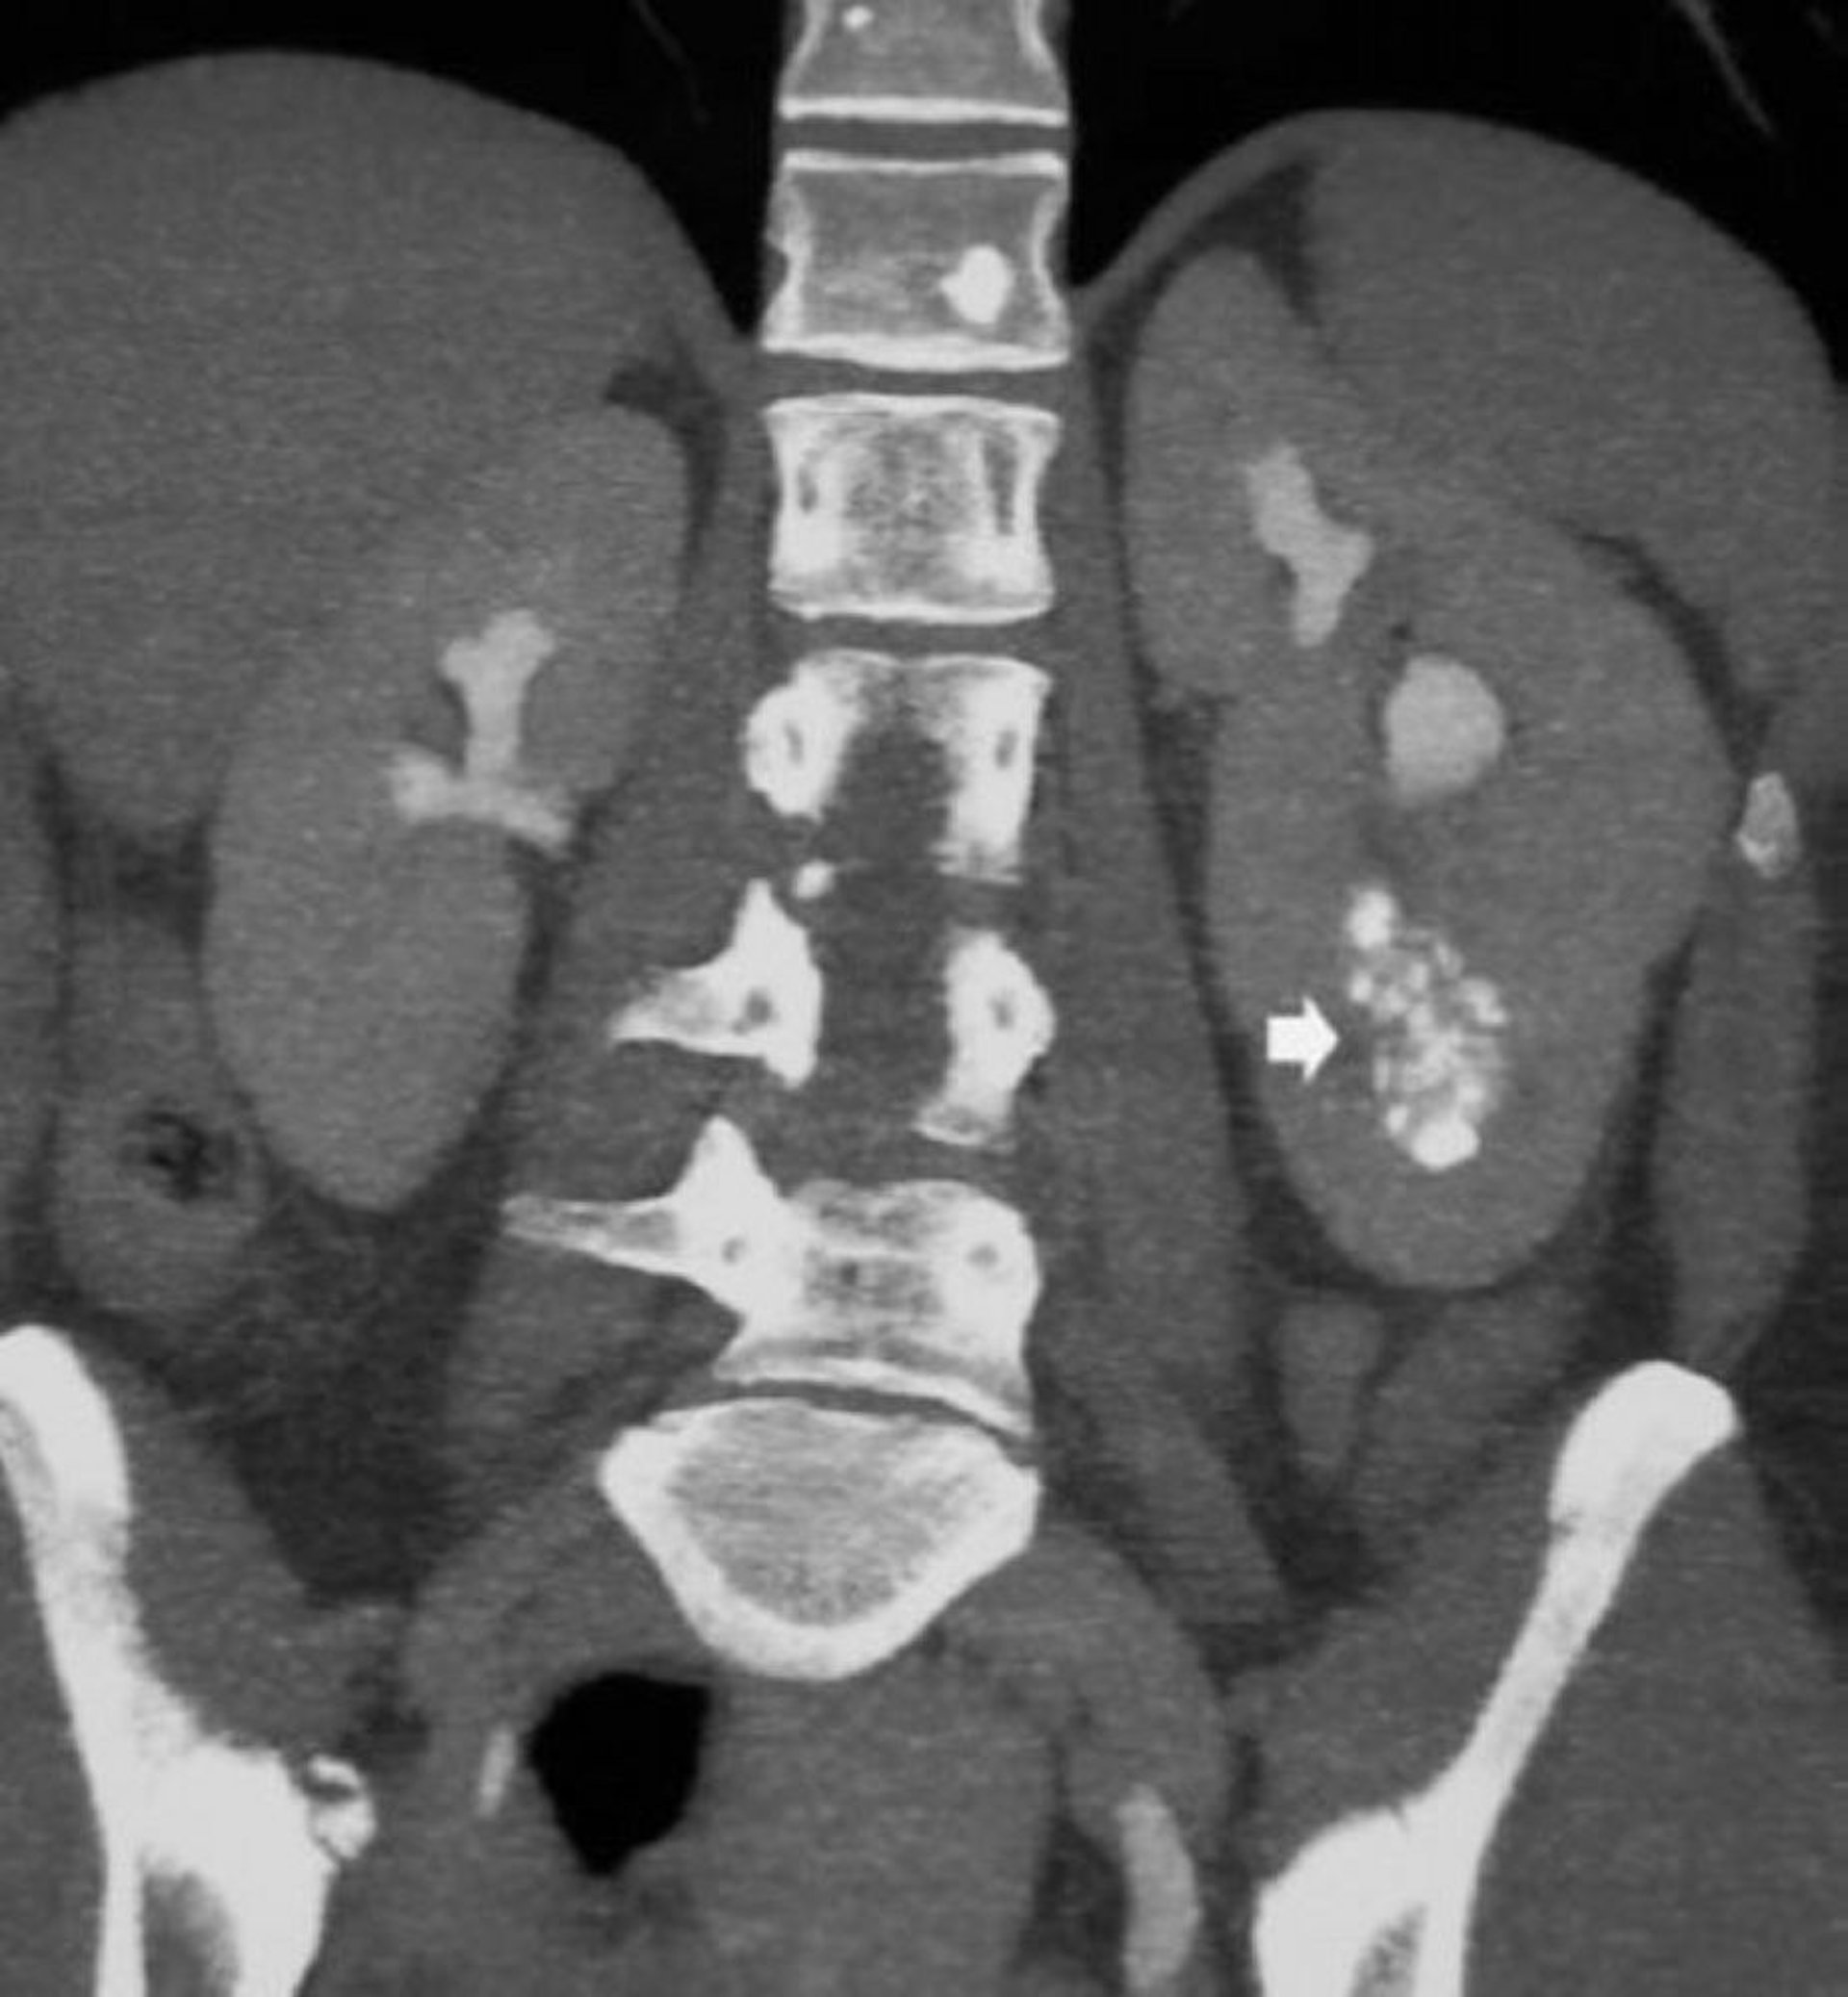

Диагноз следует подозревать у пациентов с рецидивирующим образованием камней или инфекциями мочевыводящих путей, или же на основании случайных данных рентгеновского исследования, таких как медуллярный нефрокальциноз и дилатация собирательных протоков при их контрастировании. Анализ мочи, как правило, подтверждает наличие дистального почечно-канальцевого ацидоза (манифестный метаболический ацидоз встречается редко) и снижение концентрационной способности почек у пациентов без явной полиурии.

© Springer Science+Business Media

Диагноз обычно подтверждается с помощью КТ, но можно проводить внутивенную урографию. Ультразвуковое исследование (УЗИ) не является информативным, так как кисты мелкие и находятся глубоко в мозговом слое почки.